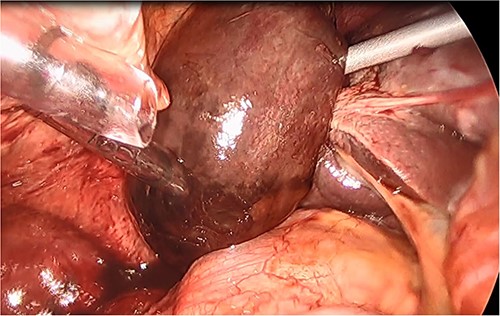

She had a good functional baseline, living in home independently and following anaesthetic review; after a family discussion, the consensus was to proceed to surgery. She underwent a laparoscopic cholecystectomy, and intraoperatively, the diagnosis of gallbladder volvulus was confirmed. A distended gangrenous gallbladder was found, which had undergone 360° clockwise rotation about the cystic duct (Figs 2, 3). The gallbladder was detorted to facilitate a traditional dissection of Calot’s triangle, achieving the critical view of safety (Figs 4, 5). The cystic duct was able to be cannulated facilitating an intraoperative cholangiogram which was unremarkable (Fig. 6). The gallbladder was then removed, and operation was completed without any complications. The histopathology of the gallbladder found diffuse haemorrhagic necrosis of the gallbladder without any evidence of dysplasia or malignancy. No cholelithiasis was present.

Gallbladder after being un-torted, showing the long cystic pedicle.